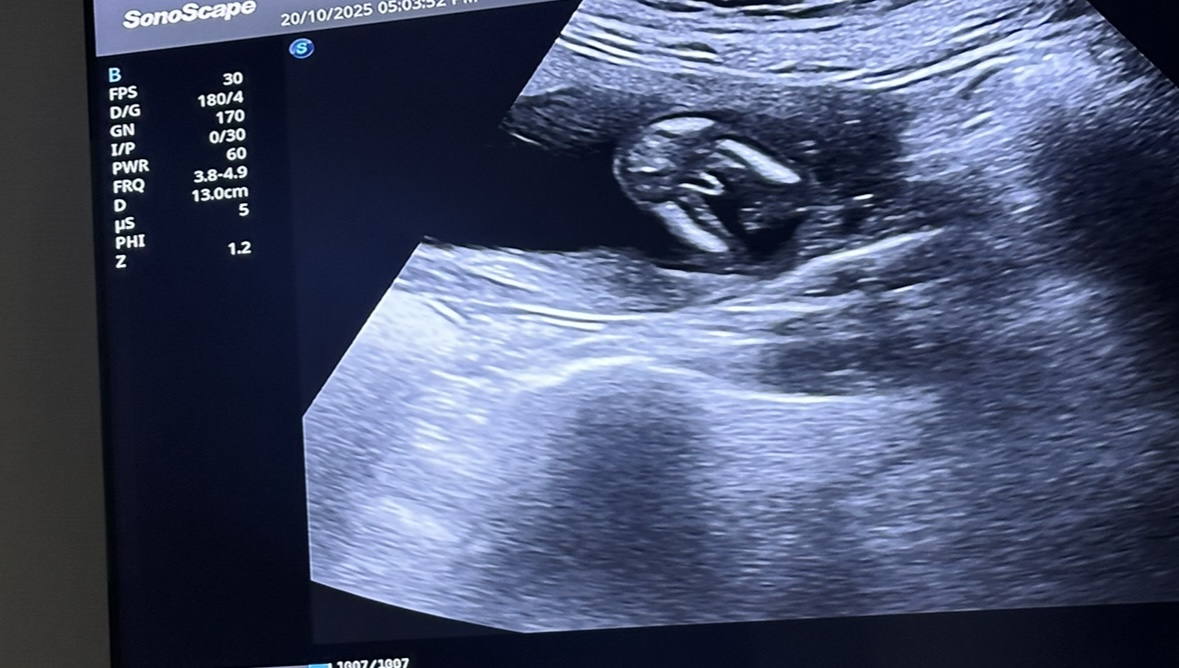

نوع الجنين في الاسبوع ١٤

شو نوع الجنين نوع الجنين بدي اعراف اذا ممكن

انا عملت سونار والدكتوره تقول لي ذكر مع انه بالنسبه لي ارى انه الحبل السري لانه كبير مقارنه بالحجم المطلوب...

السلام عليكم هل ممكن اعرف جنس الجنين من بداية الشهر الرابع ولا ايش تنصحوني باي شهر يبين